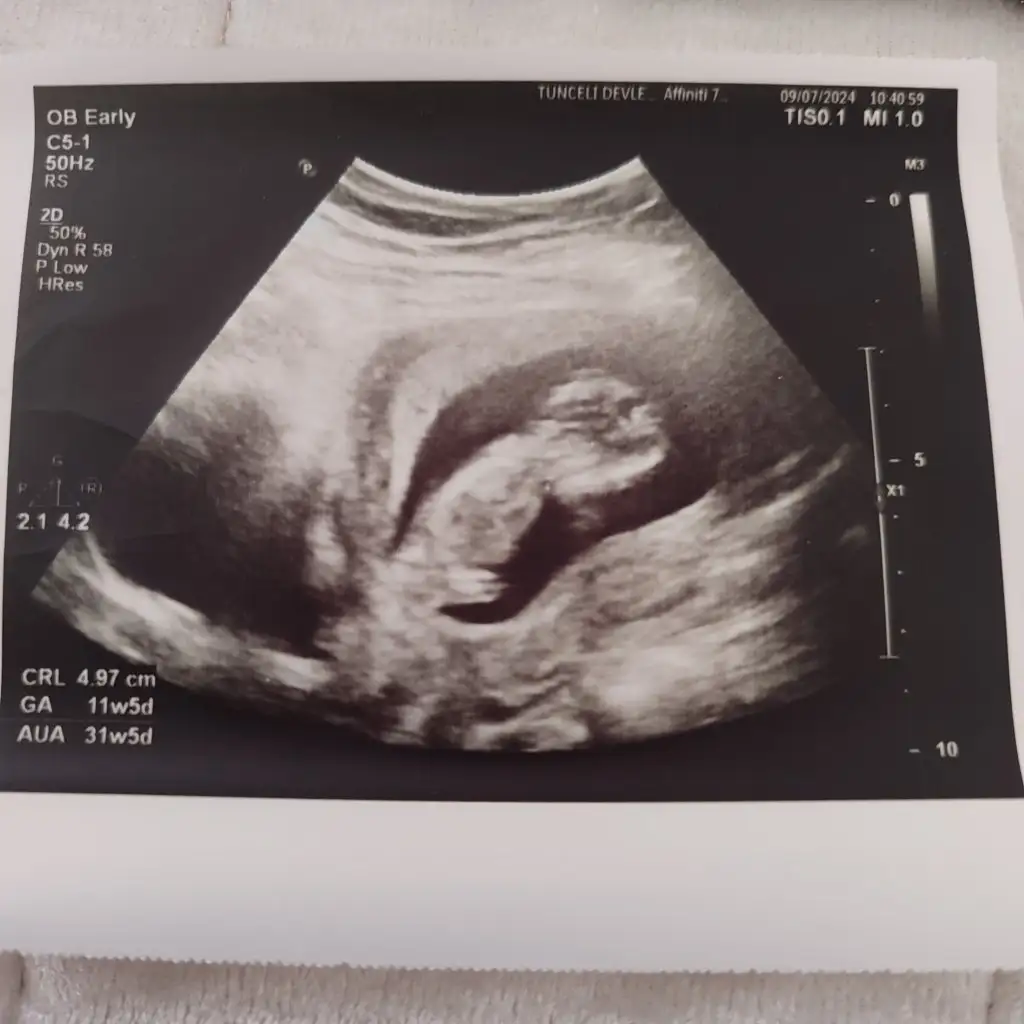

Evet kuzum ultrasyonda 8 haftalık suan 9 olmuştur , ınan hamılelıgım oğlumda gecırdıgım gibi deıl , oğlumda sureklı ekşi yerdim kısır şalgam turşu ağırlıklı tüketirdim ve sadece mide bulantım olurdu , ama bu hamılelıkte sureklı uyku bas donmesi sivilcelenme tatlı türü yeme isteği ekşi aramıyorum da , 2 sayfaya ınstgramda ultrasyon attım %70 %80 erkek dedi yanılma durumları da varmış , sadece merak sağlıklı olsun ama , artık pes ettim çevrem sureklı uyuduğum için kızın olacak diyor ama anlamadım gitti karışık yani😂

Merhaba 8 haftalık karından ultrason tahmini olan varmıdır?

• IMG_2160.webp

IMG_2160.webp

47,7 KB · Görüntüleme: 95